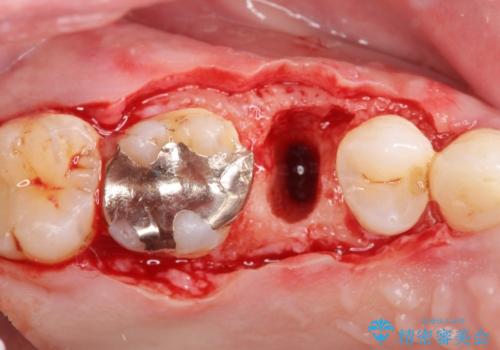

検査をしたところ、右上小臼歯に破折が見られ保存が難しい状況です。

抜歯を行い、咬合機能の回復を行いますが、咬合関係や非常に強い噛み合わせの問題をふまえ、咬合面をメタルにしたメタルボンドブリッジで治療を行うこととしました。

また噛み合わせが深くブリッジの強度が十分に確保できないことから、抜歯時に歯周外科を行うことで十分に安定したクラウン装着をできるような処置を行っています。